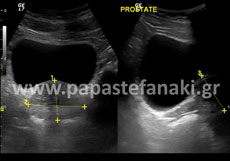

Υπερηχογράφημα Κάτω Κοιλίας - Ελάσσονος Πυέλου - Έσω Γεννητικών Οργάνων

Με το υπερηχογράφημα αυτό ελέγχουμε τα όργανα της κάτω κοιλίας και κύρια την ουροδόχο κύστη, την μήτρα και τις ωοθήκες στις γυναίκες και τον προστάτη στους άνδρες .